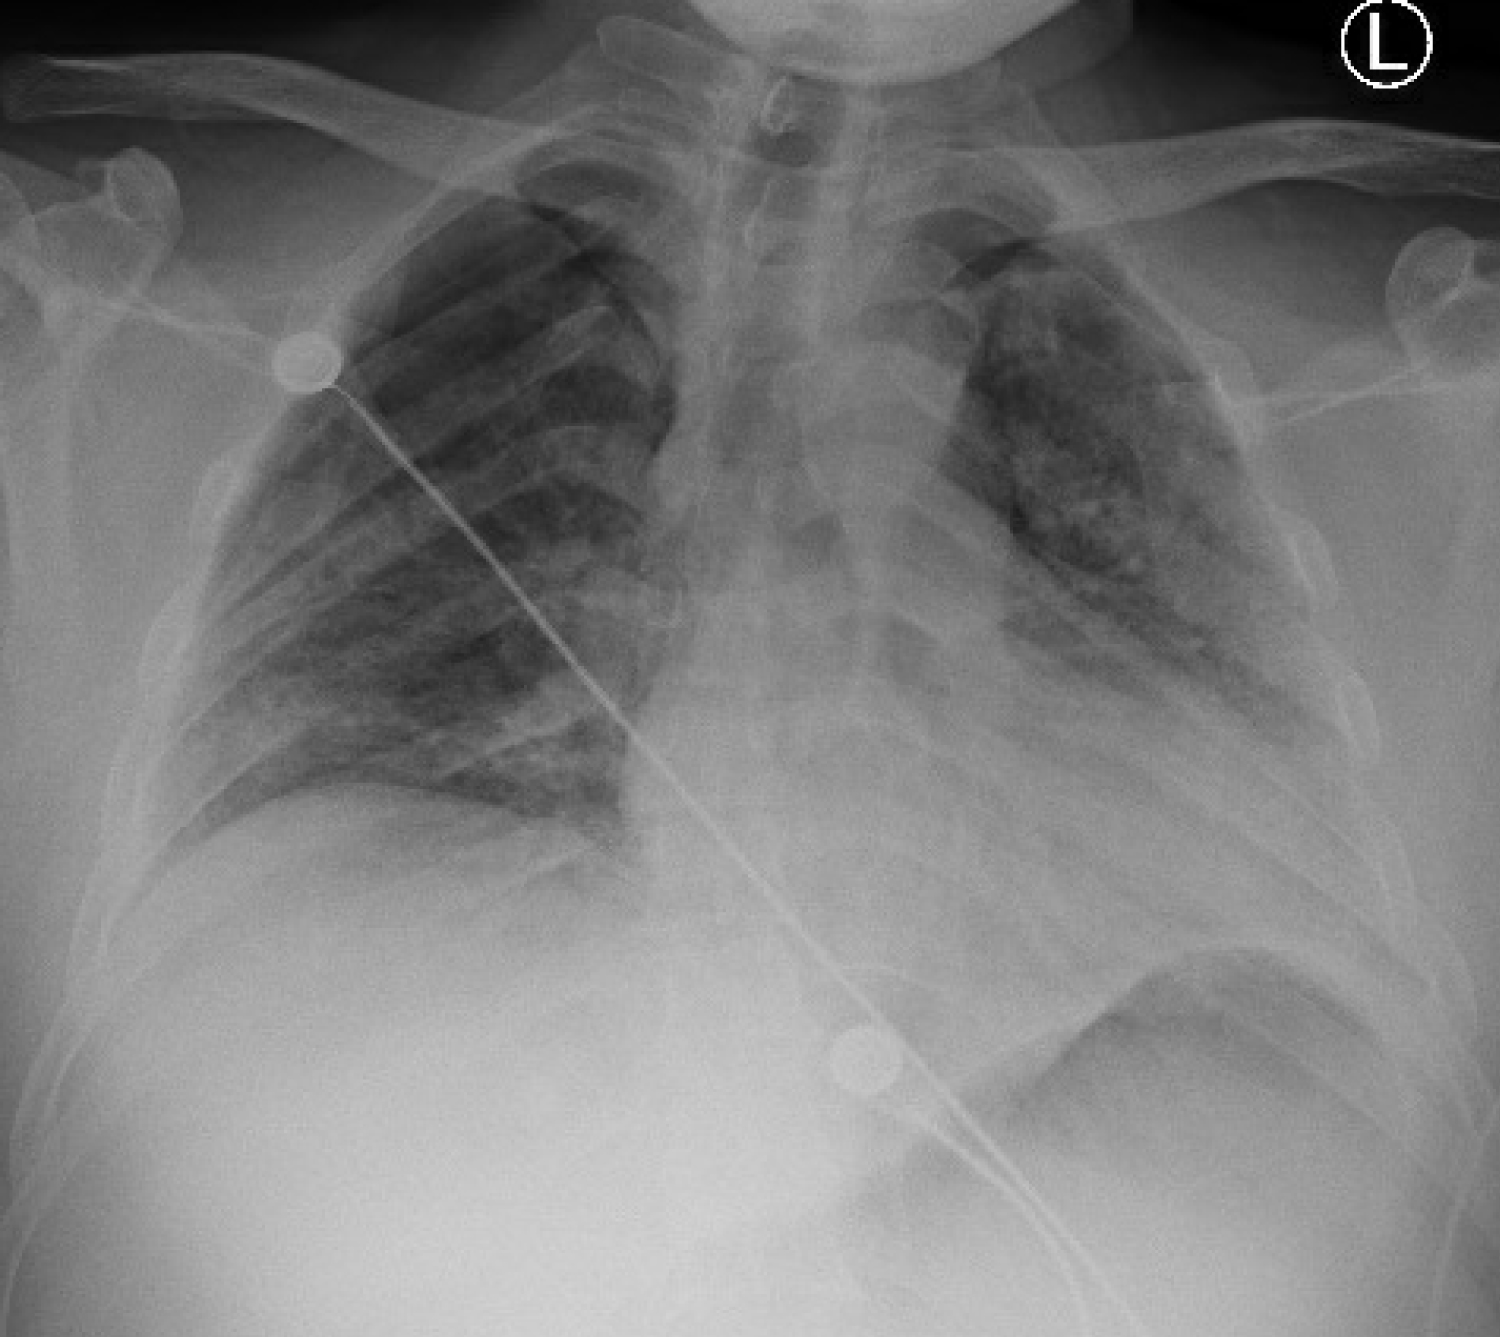

A 51-year-old obese Hispanic male, never smoker with no significant medical history was admitted with three days of cough, chills and dyspnea. On admission, his temperature was 103 degrees Fahrenheit and oxygen saturation was 88% on 100% non-rebreather mask (NRB). He was found to have severe Acute Respiratory Distress Syndrome secondary to SARS-CoV-2 viral pneumonia, with a PaO2:FiO2 ratio of 68. Admission labs revealed normal WBC count, CRP elevated at 10.1 mg/dL, LDH elevated at 439 U/L, D-dimer elevated at 0.40 ug/mL and ferritin elevated at 489 ng/mL. His chest X-ray showed bilateral diffuse infiltrates. He was treated with a course of hydroxychloroquine, azithromycin, and methylprednisolone. He received tocilizumab and convalescent plasma. He continued to require 100% NRB mask to maintain his oxygenation. On day 15 of his hospitalization, he developed sudden chest pain and worsening hypoxemia. Chest X-ray revealed right sided apical pneumothorax and pneumomediastinum (Figure 1). He had a chest tube placed with improvement in his oxygenation. His pneumothorax and pneumomediastinum resolved after which chest tube was removed. He was discharged to rehabilitation facility on oxygen therapy 3 liters per minute nasal cannula. He had a CT thorax done eight weeks later which showed peripheral ground glass opacities with bronchiectasis. No significant underlying bullous lung disease noted. There was also no evidence of residual pneumomediastinum.

Figure 1: Pneumomediastinum with small right apical pneumothorax. View Figure 1